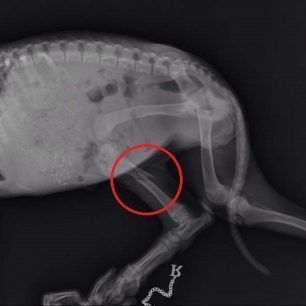

Το κουταβάκι που βλέπετε στις φωτογραφίες εντοπίστηκε χθες στο Άκτιο να κλαίει από τους πόνους κοντά στα διόδια της υποθαλάσσιας σήραγγας καθώς όπως αποδείχτηκε έχει σπασμένα τα δύο πόδια του ενώ είναι χτυπημένο και στην κοιλιά. Το πως τραυματίστηκε το ζώο παραμένει άγνωστο αν και σύμφωνα με τον κτηνίατρο Νίκο Ρώσσο, που το εξέτασε, κάποιος είναι πολύ πιθανό να το το κλώτσησε.

Η Δώρα Τσάτση μέλος του σωματείου «Παρέμβαση για τα Ζώα - Πρέβεζα» εξήγησε στο www.zoosos.gr ότι ο κ. Ρώσσος τους είπε πως είναι απίθανο το κουταβάκι, που ζυγίζει μόλις τέσσερα κιλά, να χτυπήθηκε από όχημα καθώς δεν έχει σημάδια και αυτά τα τραύματα προκαλούνται μόνο από κλωτσιά.

Εξαιτίας του νεαρού της ηλικίας του κουταβιού δεν θα γίνουν όλες οι επεμβάσεις ταυτόχρονα. Αρχικά θα χειρουργηθεί στην κοιλιά και στην συνέχεια θα ακολουθήσουν οι επεμβάσεις στο πίσω πόδι του που έχει σπάσει σε δύο σημεία και στη συνέχεια στο μπροστινό.